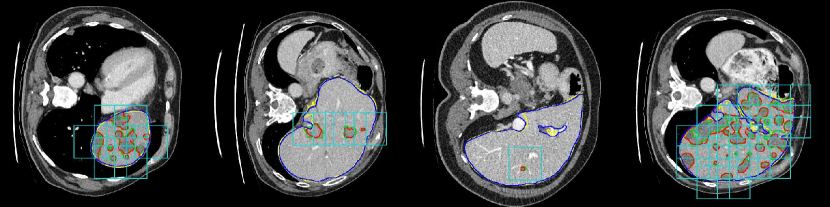

Refer to caption

Figure 2: Results of the lesion detection network. Blue and red lines indicate the liver and lesion ground truth, respectively. Yellow and green lines are the segmentation results for liver and lesion. The light blue bounding boxes are the windows detected as having a lesion. All positive pixels at the output of the segmentation network will be removed if they disagree with the results of lesion detection.

In order to train the detector, we place bounding boxes in the liver region and then label them as positive or negative. The condition in order to place a bounding box is that it overlaps at least 25% with the liver. We use windows of 50×\times50 pixels, considering a positive observation if there are at least 50 pixels of lesion inside the box. The stride is 50 pixels, and 15 pixels of margin are added to every side of the window to provide additional context, so that each window is finally of size 80x80. The model we used is ResNet-50 [6] pre-trained on ImageNet, removing its last classification layer and replacing it by a single neuron to detect healthy/unhealthy liver tissues. We use a batch size of 64 equally balanced positive and negative patches. We augment the data by a factor of 8 using flipping and rotation.